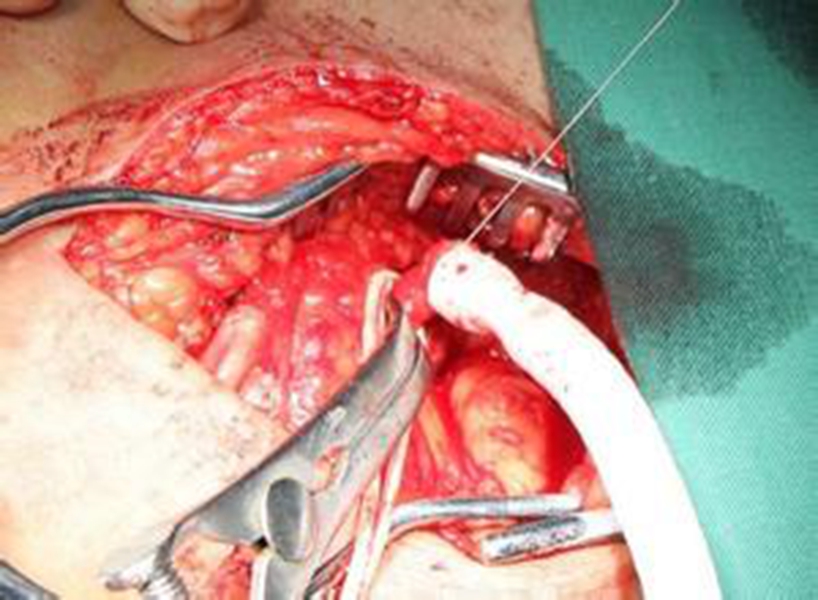

幼兒頸部手術煙霧病

A:煙霧病目前有兩種手術方式,分別是血管搭橋手術和血管貼敷手術。血管搭橋手術是將顳淺動脈進行剝離,然後與大腦中動脈進行吻合搭橋。而血管貼敷手術是將顳淺動脈剝離後貼敷到腦的表面上。通過這兩種手術方式,主要的起到的作用是建立新的側枝循環,從而供應腦……

A:煙霧病的主要手術方式是進行顳淺動脈搭橋手術或者貼敷手術,這種手術是需要進行全身麻醉的,因此做完手術後需要臥床,並且密切觀察病情變化。如果術後恢復順利,那手術後兩三天就可以開始下床活動,早下地能夠起到改善下肢循環的作用,能夠預防出現下肢的深靜……